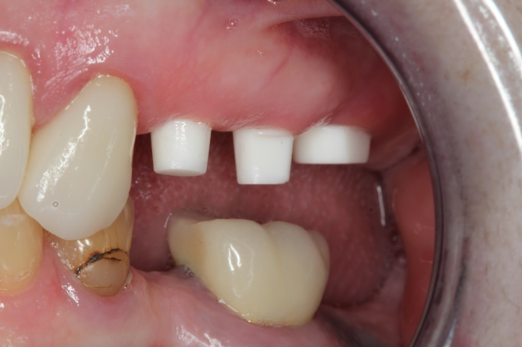

Fig 6. After splint removal (12 weeks postoperatively).

Figure 6

Fig 7. 12 weeks postoperatively.

Figure 7

Figure 3 through Figure 5 show the fitting of a one-piece multiple splint using a light-cured acrylic, along with flowable composite to adhere the splint to the three ceramic dental implants. The splint was to remain out of occlusion, without any occlusal forces for the 12-week osseointegration period. The patient was instructed to chew on the other side of her mouth for the 12 weeks before returning to the dental practice for simple removal of the splint. Removal of the splint revealed optimum results. The soft tissues were pink, with keratinized gingival margins completely surrounding the ceramic implants and consistent with what most dentists observe with the periodontium around periodontally healthy natural teeth (Figure 6 and Figure 7).